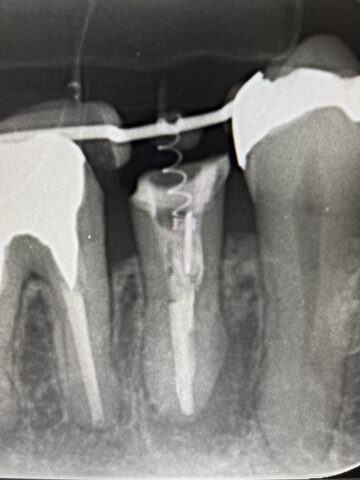

エクストリュージョンで、歯の脱臼を術前に施行

-

意図的再植のための抜歯及び、歯根膜へのエムドゲイン塗布